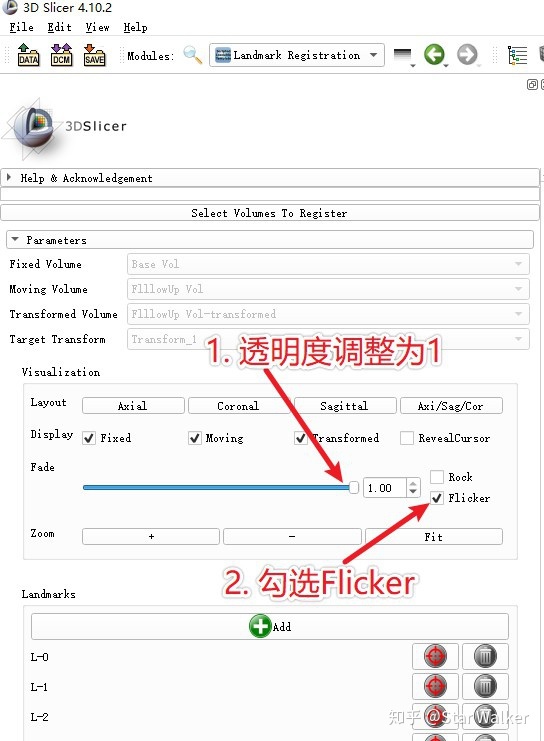

添加标志点之前,建议先按照下图进行操作,尤其是先按照下图中的第一步和第二步,选择参数设置。第一步和第二步的基本想法是,先从一个最基础的、也是最好调整、不容易出错的空间变形方式开始,先把两套数据基本对齐了,再切换到更复杂、更精准的空间变形方式上,取得更好的配准效果。关于选项1和2的具体含义,咱们后面再细说。

- 推荐随时勾选和取消勾选左侧的“Flicker"框,通过观察第三行的交替切换显示窗口,来确定固定和浮动图像的当前对齐程度。(操作参见第12条下方的图片)

下面的图片说明了如何打开Flicker开关,观察图像对齐效果。